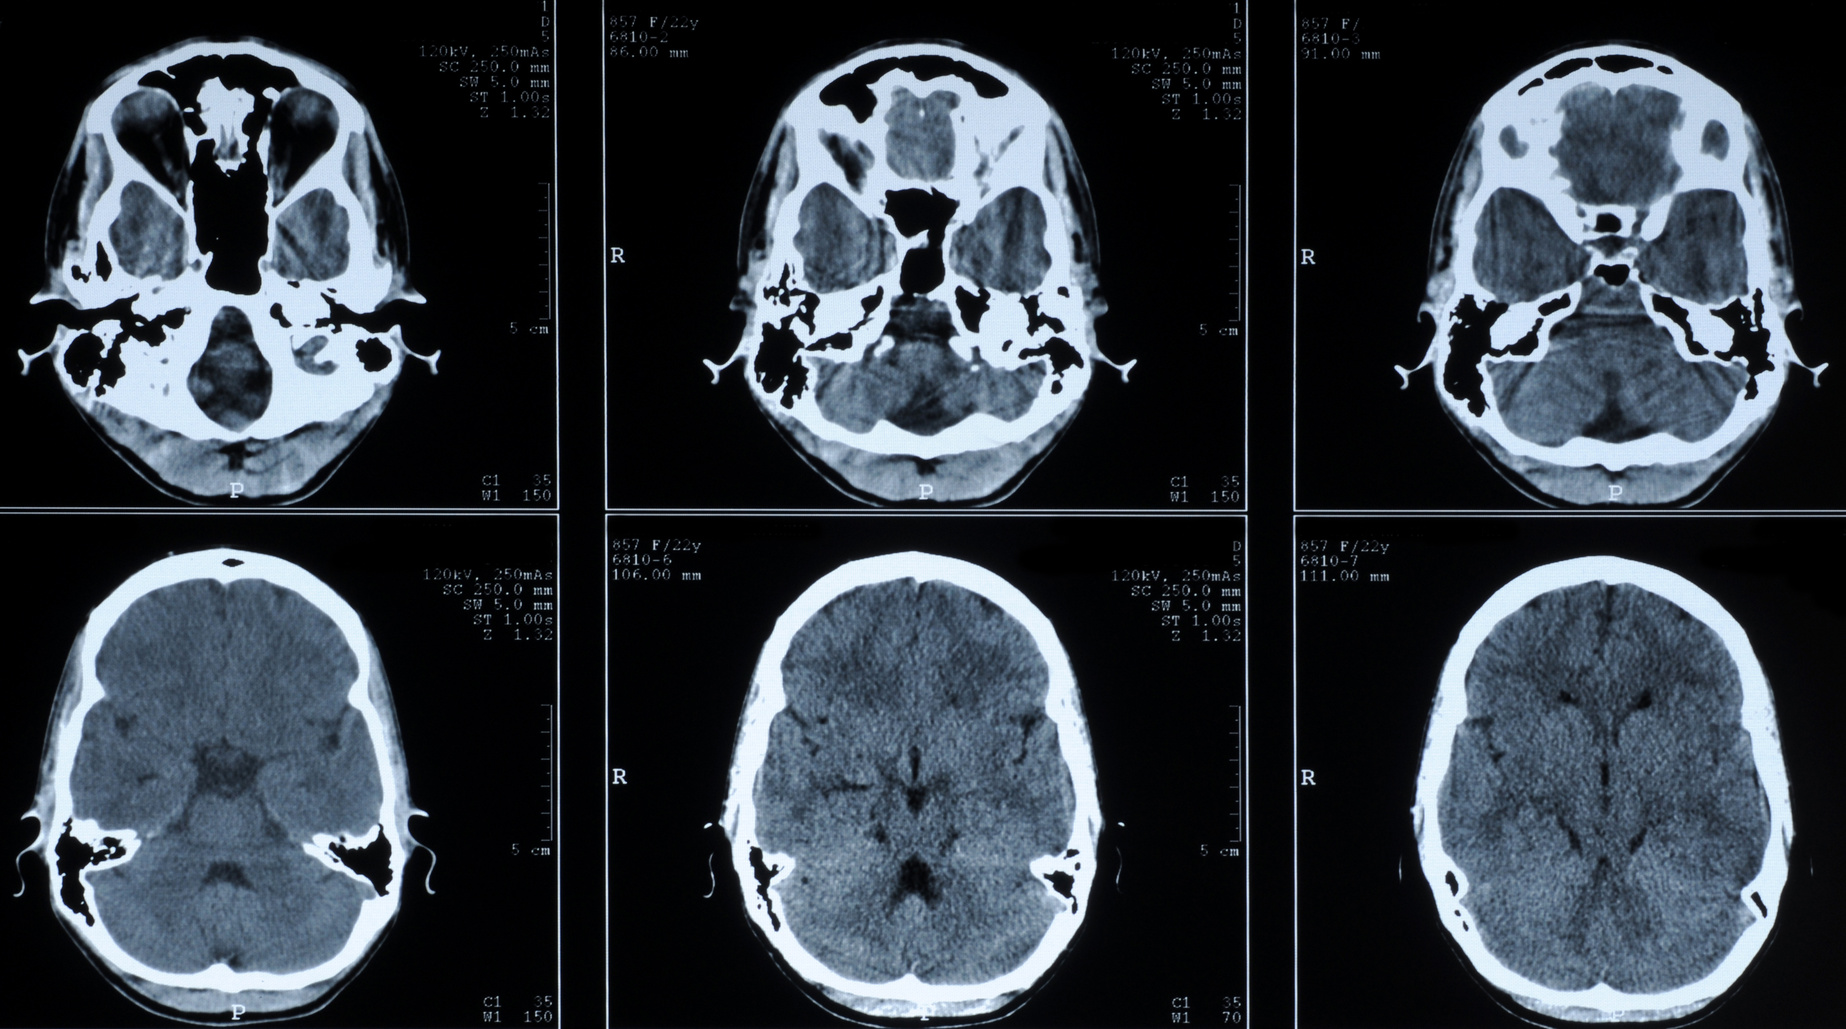

W Szpitalu Morskim im. PCK uruchomiony został właśnie 64-rzędowy aparat TK do wirtualnej symulacji o parametrach umożliwiających badania 4D (z ruchomością oddechową).

Aparat przeznaczony jest przede wszystkim dla pacjentów onkologicznych i służy do wykonywania najbardziej zaawansowanych badań diagnostycznych metodą wielowarstwowej tomografii komputerowej. Zapewnia najwyższą wydajność i jakość obrazowania, podnosząc jednocześnie standard świadczonych usług medycznych w gdyńskiej placówce.